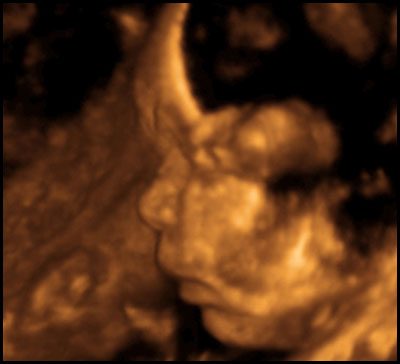

First, some notes on what you're seeing, in case some of these graphics seem a little weird. The machine only captures 3D images in a small area, and anything outside the area is either not visible or appears as blurriness. Also, while the technician tried for a good face shot, the baby's head was partially smooshed against the placenta the whole time, so it was never possible to get a really clear eyes/nose/mouth image.

Anyway, here he is....toes and all.

You guys. That's my SON in there! My god, I can't wait to meet him.